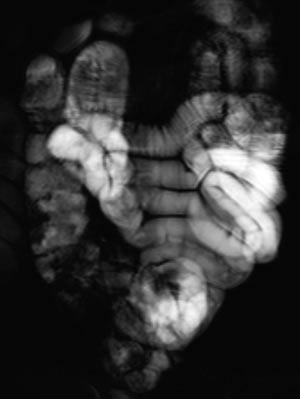

Indikasjoner for MR av tynntarm

Vanlige MR-funn ved Crohns sykdom er fortykket tarmvegg (fig 5). Mer overflatiske forandringer i slimhinnen blir ikke optimalt fremstilt, men dypere ulcuser blir fremstilt, og dette er tegn på aktiv inflammasjon (fig 6). Både fibrose og aktiv inflammasjon i tarmveggen lader opp etter intravenøs kontrast. Det typiske for aktiv inflammasjon er en kraftig og lagdelt kontrastoppladning (fig 7), men den kan også være mer homogen.